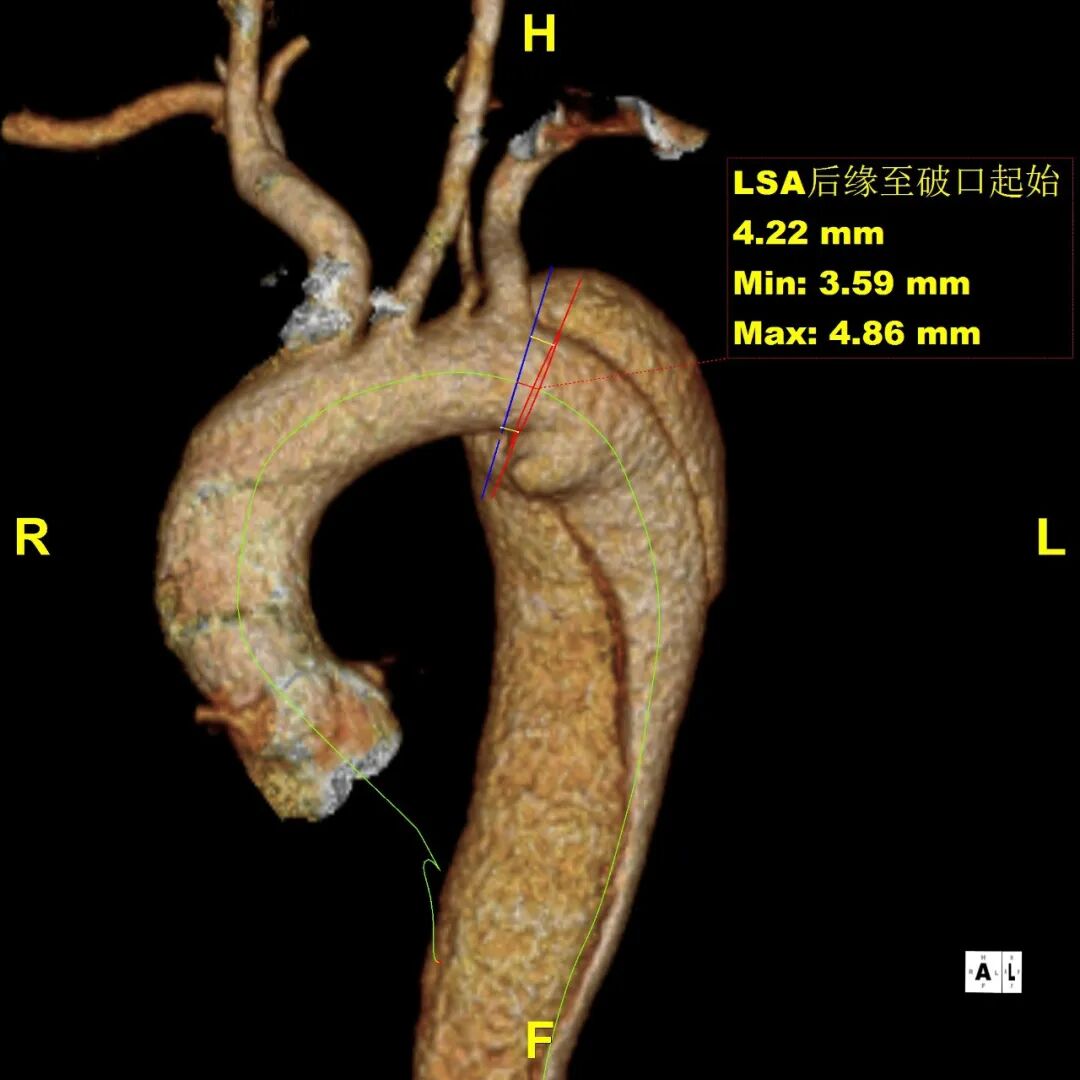

患者 10月前因“梗阻性黄疸、胆总管结石”检查发现主动脉夹层B型,否认腹痛、腰背痛,追问病史,2019年曾出现胸痛,行冠脉造影未见异常,当时血压170mmHg。诊断为:B型主动脉夹层累及到LSA后缘,左侧椎动脉发自于主动脉弓上的变异解剖形态

gore医疗怎么样「胸有乾坤」释半功倍 得心应手——GORE®TAG® 可主动调控胸主动脉覆膜支架治疗B型主动脉夹层病例分享 复旦大学附属中山医院_https://www.jmylbn.com_新闻资讯_第12张